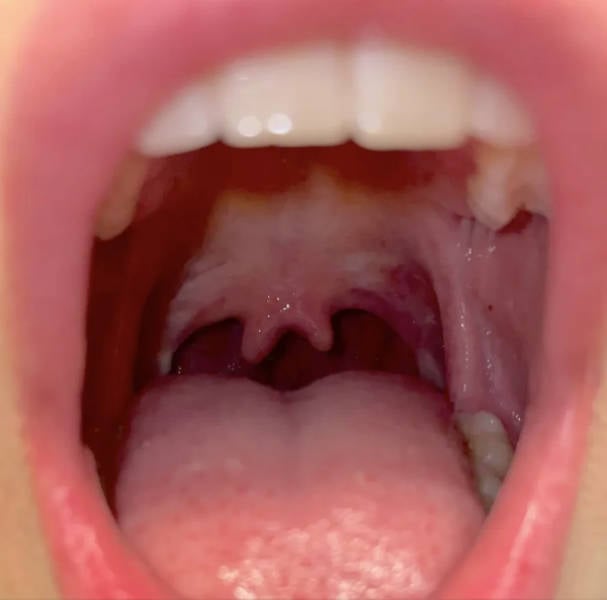

"Behold: A double uvula."